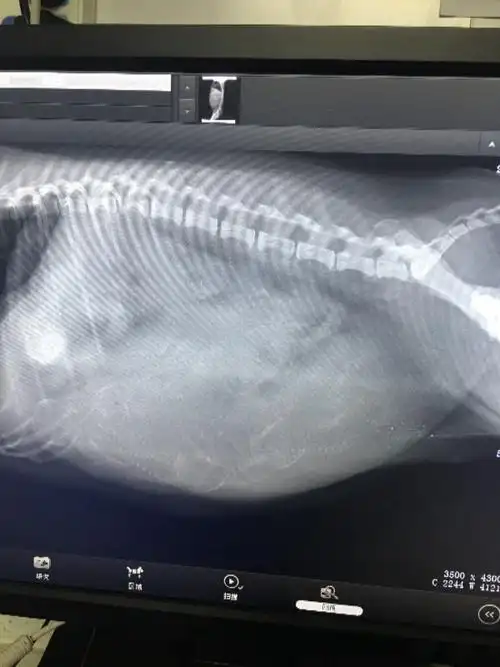

最近带ollie宝去拍了x光片之前看乳头有5个变大猜有五个宝宝为了确定

介绍承诺:坐标福州,自己家的泰迪宝宝的第一胎,昨天照了x光一共有5只

【求助】请问有会看x光片的吗?或者根据狗狗情况提供一些信息.